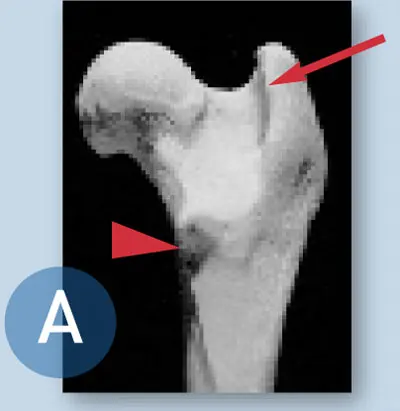

Landmarks for the femoral head and neck are now visible and include the medial aspect of the base of the greater trochanter (arrow) and lesser trochanter (arrowhead), located on the medial cortex of the femur. With adequate elevation of the origin of the vastus lateralis muscle, direct palpation of the lesser trochanter is possible and should be performed. The lesser trochanter is best appreciated as a small “bump.”

The insertion of the iliopsoas muscle is also palpable at or slightly distal to the lesser trochanter. Ideally, this muscular insertion is preserved during the excision of the femoral neck, but not at the expense of eliminating bony contact of the medial femoral cortex with the pelvis.

A shows the femoral head and neck prior to ostectomy; B shows how the femur should look when the correct cut is made during ostectomy.